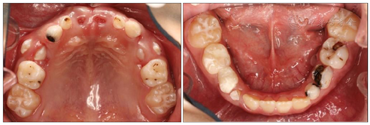

混合牙列,51、61口内未见;16、26、36、46均萌出;14、24萌出,松动I度;84MOD、85O、B大面积白色样充填物;73MD、74MOD、75DO龋洞;83无松动,仅余留牙根;53D、55O、P、65O、P龋坏;52、62松动Ⅱ度,腭面近中呈黄褐色。牙龈粉红,质地韧、探诊无出血,上下牙列唇舌侧牙颈1/3有软垢附着。dmft为15。

X线影像显示:73M、D透射影像,达牙本质中层,根尖周未见异常。74MOD透射影像,近髓腔,根分叉处可见透射影像,34恒牙胚硬骨板完整,根尖周未见异常。75DO透射影像,近髓腔,根分叉处可见透射影像。远中根尖周可见透射影像,波及35恒牙胚硬骨板。55O、P、65O、P龋坏,探诊质硬,冷诊正常,叩痛(-)。14、24萌出,松动I度,牙合面近远中向牙龈覆盖(图4)。

X线影像显示:14、24未见牙根影像。53D龋洞,发黑,探诊硬,冷诊正常,叩痛(-),根尖区黏膜无异常(图5)。X线影像显示:53D透射影像,达牙本质中层,根尖周未见异常。52、62松动II度,腭面近中呈黄褐色,探诊质硬。51、61拔牙创区牙龈无红肿,牙龈黏膜未完全愈合。16、26、36、46牙面窝沟白色样封闭物,封闭物完好(图6)。